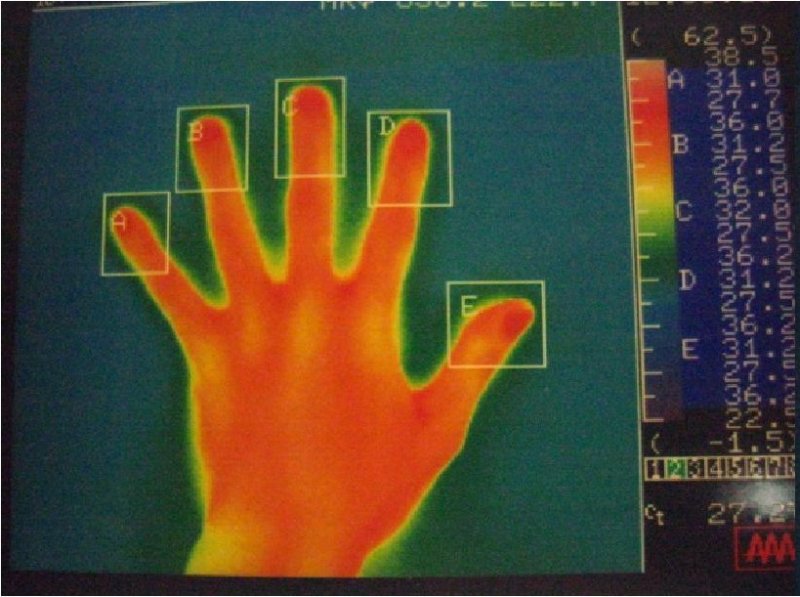

サーモグラフィー

左手

右手

赤い部分が高温部位を示しています。